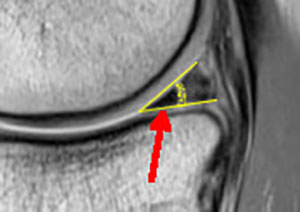

Le ménisque s'use avec le temps : il prend un aspect dégénératif sur l'irm sous la forme d'une fissure oblique blanche (ici surlignée en jaune) dans l'épaisseur du triangle méniscal.

Ces lésions dégénératives sont à priori indolores et anciennes. L'aspect de la surface méniscale est normale en arthroscopie et l'ablation d'une telle "lésion" est sans effet sur les douleurs du patient (par contre très dommageable pour le cartilage...)

La découverte de cette lésion est habituelle par une IRM chez un(e) patient(e) autour de 50 ans, mais cette lésion bénigne peut être observée plus tôt dans la vie (25-30 ans).